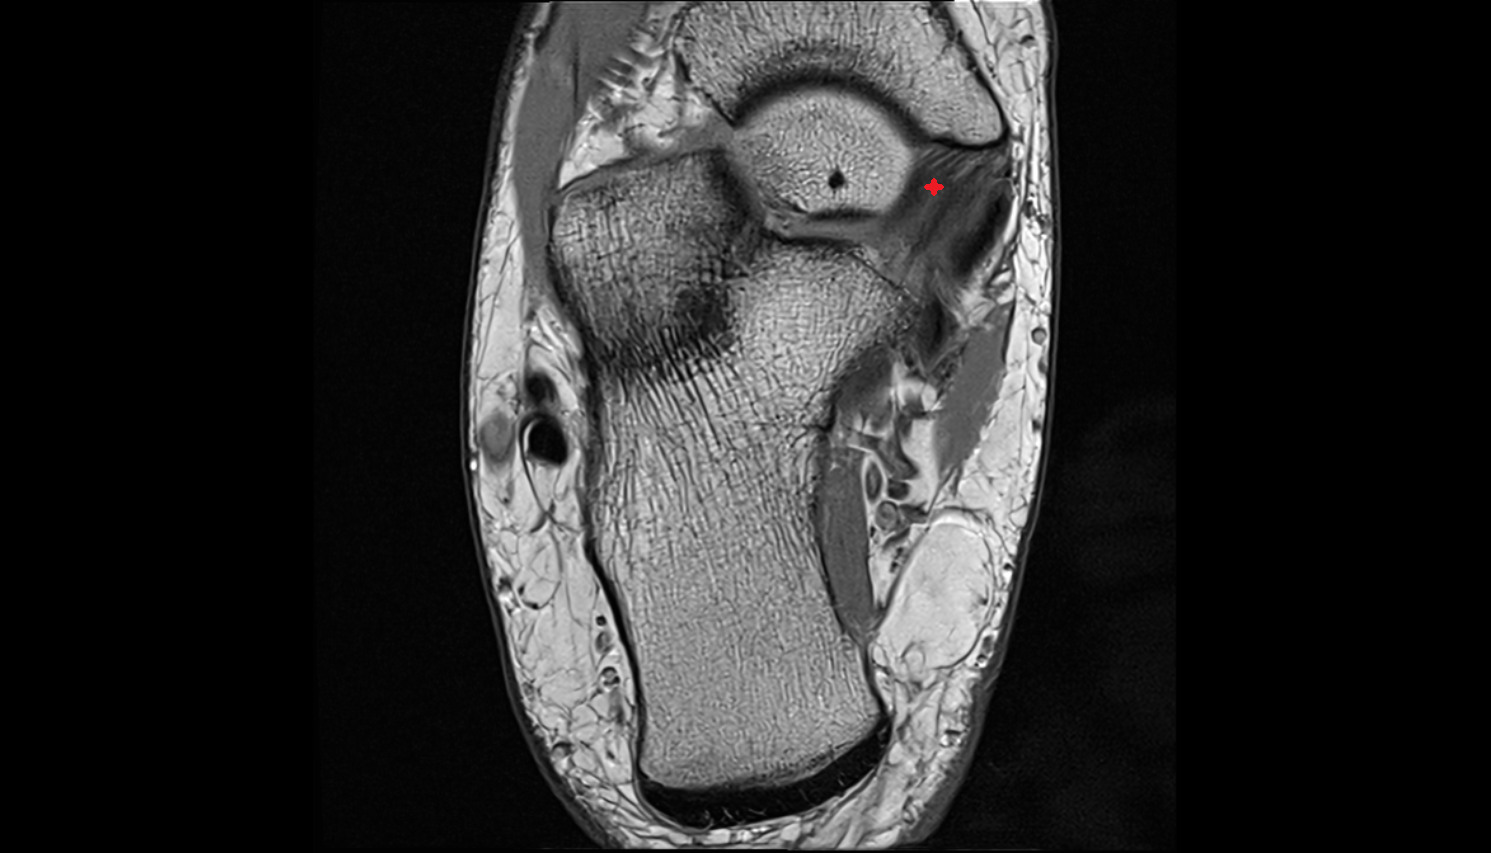

- Ankle joint

- Talus

- Calcaneus

- Medial malleolus

- Lateral malleolus

- Sustentaculum tali